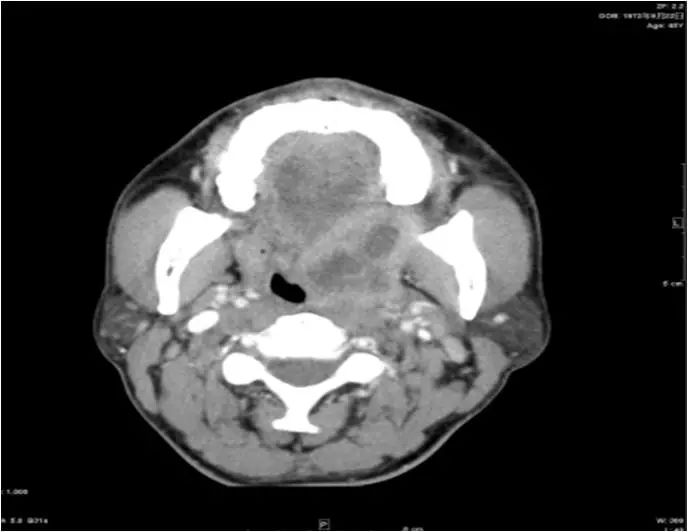

15 多间隙受累

(1)左下后牙疼痛11天余,颈部肿胀10天。

(2)右侧颌面部弥漫性肿胀1月余。